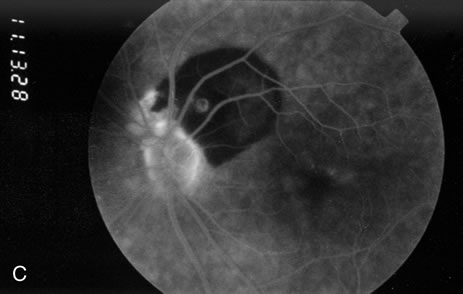

Fig. 3. A. Color fundus photograph of a macroaneurysm along the inferotemporal arcade with surrounding intraretinal and subretinal hemorrhage. There is retinal edema, hard exudates, and thin subretinal hemorrhage extending into the macula. B. Midphase fluorescein angiography reveals hemorrhage that extends just into the foveal avascular zone, threatening foveal vision. C. Late-phase angiogram reveals staining of the macroaneurysm. D. Color fundus photograph of the same macroaneurysm 6 weeks after laser photocoagulation, demonstrating resolution of the edema and hemorrhage.

Because of rapid blood flow through retinal arterial macroaneurysms, they typically fill quickly in the early phase of the fluorescein angiogram. In the mid- and late-phases of the angiogram, the macroaneurysm tends to leak to varying degrees, depending on its perfusion and endothelial integrity (Fig. 3C). If there is subretinal fluid surrounding the aneurysm, there may be pooling of dye into the subretinal space. In some cases, a characteristic Z-shaped kink may be identified at the site of the aneurysm.

Perfusion abnormalities caused by the macroaneurysm cause changes in the surrounding retinal vasculature as well, and this is best visualized on fluorescein angiography (Fig. 3B). Ischemia from stagnation of blood flow results in capillary telangiectasis, microaneurysm formation, and capillary nonperfusion.

Some or all of these angiographic features may be obscured by blood or lipid exudation from the aneurysm. If blood collects in front of the retinal vessels (vitreous hemorrhage, preretinal hemorrhage, subinternal limiting membrane hemorrhage, or intraretinal hemorrhage), then blockage of hyperfluorescence may be partial or complete. Subretinal blood blocks hyperfluorescence from the choroid but not the retinal circulation, resulting in dramatically distinct retinal vessels against a dark background (Fig. 3B,C). Lipid exudation and retinal edema may cause partial blockage of hyperfluorescence.